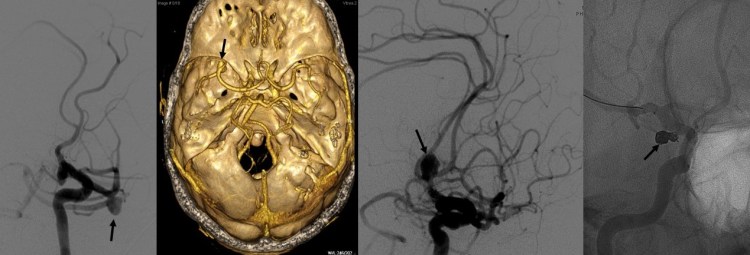

- Aneurismas cerebrales: Representan la causa más frecuente de hemorragia subaracnoidea espontánea (75-80% de los casos). Se trata de dilataciones de las arterias debidas a la debilidad en la pared de las mismas. Ello provoca que pueda tener lugar la ruptura de la arteria con la consiguiente hemorragia. La frecuencia de aneurismas cerebrales en la población se sitúa en torno a un 1-5%. En caso de ser diagnosticados inmediantamente tras una hemorragia subaracnoidea deben ser tratados tan pronto como sea posible para minimizar el riesgo de resangrado. En otras ocasiones tiene lugar el diagnóstico de aneurisma cerebral en pacientes asintomáticos sin que se haya producido la ruptura del mismo. En estos casos ha de valorarse la posibilidad de tratar el aneurisma de forma preventiva para evitar que en un futuro tenga lugar la hemorragia subaracnoidea. Tanto en un caso como en otro, el tratamiento puede llevarse a cabo de forma endovascular, mediante cateterismo cerebral, o bien mediante cirugía la cual permite el clipaje y cierre definitivo del aneurisma. La decisión sobre el tratamiento y la elección de una técnica u otra va a depender fundamentalmente de la localización del aneurisma, sus relaciones anatómicas con las ramas arteriales afectadas, el tamaño de mismo, la edad y condición clínica de cada paciente.